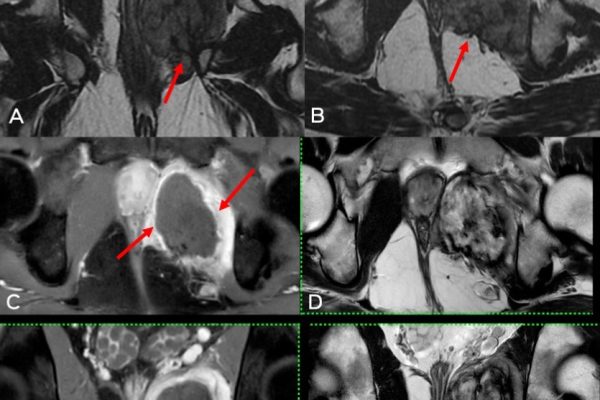

During the stereotactic breast biopsy, mammographic imaging is used to locate areas of interest in the breast tissue. It is highly accurate in gathering tissue samples from small, not easily accessible, or non-palpable abnormalities. The radiologists use a computer and 3D imaging, thereby guiding a needle to the anomaly’s exact location, making this procedure both efficient and accurate.

Once the region is anaesthetised, the radiologist will introduce the biopsy needle by means of a small incision. The stereotactic biopsy procedure needs computer guidance to allow the insertion of the needle to accurately position where desired. The method can also be applied using a vacuum-assisted device that can help in acquiring several tissue samples through one single incision in minimal time.